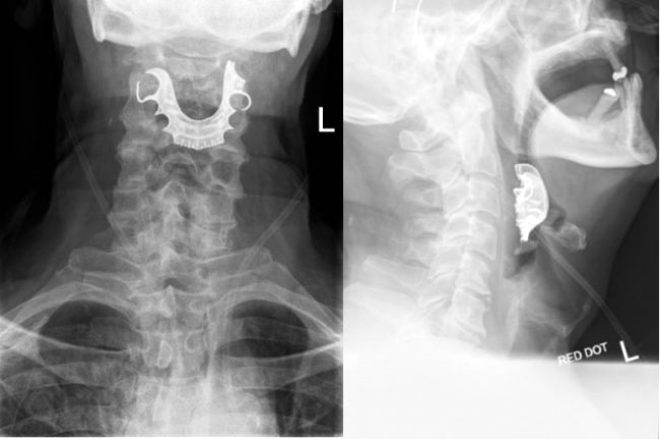

Hastanın boğazına kaçan takma dişleri, ameliyattan 8 gün sonra fark edildi.

Hasta, ameliyat sonrası yutkunmada sorun yaşadığından, öksürükten ve öksürükle birlikte kan tükürmekten şikayet etmeye başladı.

Karın bölgesinden rutin bir ameliyat geçiren erkek hasta, bu şikayetlerle birçok kez hastaneye gitti, yeni ameliyatlara girdi ve kan nakilleri yapıldı. Norfolk bölgesindeki James Paget Hastanesi, yaşananların ardından hasta bakım sürecinde değişiklikler yapıldığını açıkladı.

Hastanın başına gelenler, bilimsel yayın İngiliz Tıp Dergisi'nin Vaka Raporları bölümünde yayımlandı. Uzmanlar, hastanın ameliyattan önce genel anesteziyle uyutulmasından önce, takma dişlerin çıkartılmış olması gerektiğini vurguladı.